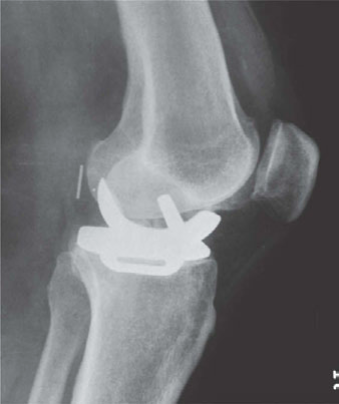

(Figure 3.4.) CANDIDATE : This is a weightbearing AP radiograph of left knee demonstrating moderate medial compartment osteoarthritis. The lateral compartment appears normal. There is a varus deformity of less than 10. I would like to take a history and examine the patient. The examination is focused mainly on localizing the tenderness, range of motion, if the varus deformity is correctable and stability of knee.

Figure 3.4

Anteroposterior (AP) radiograph knee. EXAMINER : The patient is fit and well, states that the pain is affecting his job and he would like to consider a surgical option. What would you offer him? CANDIDATE : The options of surgical management once conservative measures have failed include HTO, unicondylar knee arthroplasty or total knee replacement. Since this patient has a high-demand physical job, I would offer him HTO. EXAMINER : What are the prerequisites of HTO? CANDIDATE : A physiological age of < 60 years, fixed varus deformity < 15 or valgus deformity < 12, fixed flexion deformity of < 15, > 90 flexion. EXAMINER : Are you aware of any contraindication for HTO? CANDIDATE : The main contraindications are inflammatory arthropathy such as rheumatoid arthritis and psoriatic arthropathy, incompetent medial collateral ligament or ACL, large varus thrust with coronal subluxation of > 1 cm, severe OA of medial compartment or lateral compartment/PFJ and more than 20 of correction. Obesity is also a contraindication because valgus knee is poorly tolerated due to medial thigh contact. EXAMINER : The patient tells you that he has heard about partial knee replacement and is keen to consider the option. How do you proceed? CANDIDATE : I would explain to the patient that UKA is an option; however, I would not recommend UKA for this particular patient because the highly physically demanding job could result in accelerated wear of UKA. EXAMINER : So which patients would you offer UKA? CANDIDATE : The indications and prerequisites for HTO and